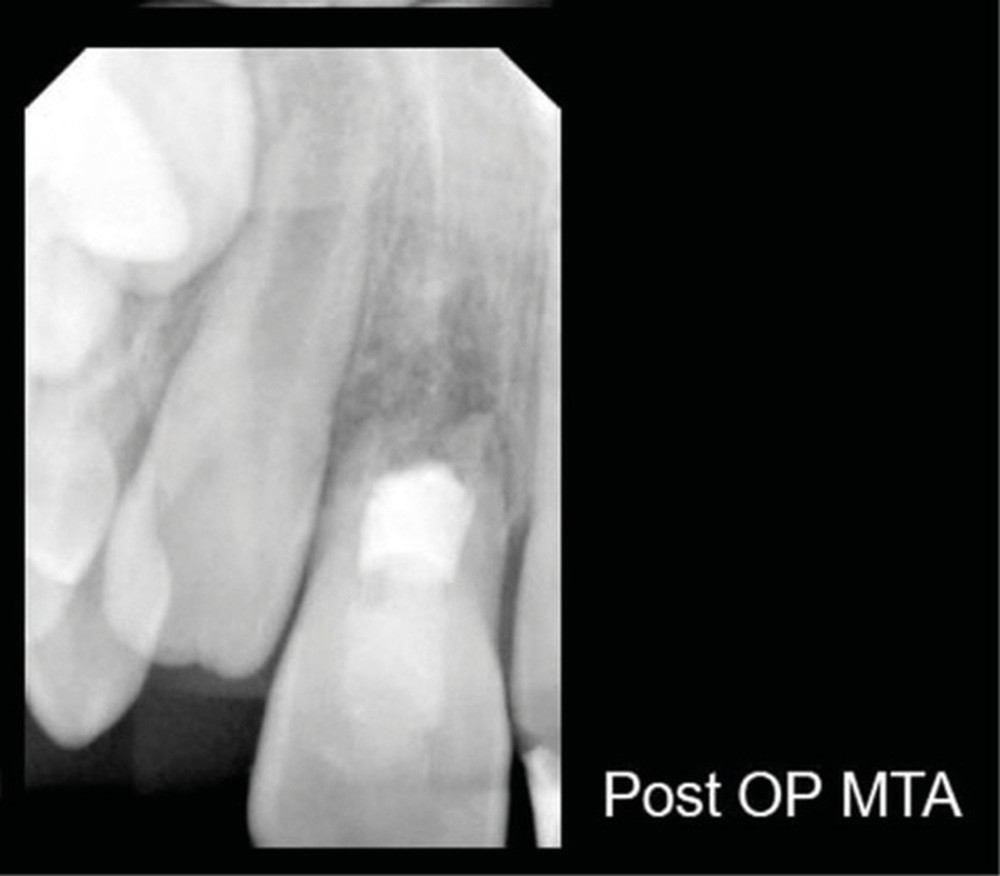

Ce cas clinique est particulier et illustre parfaitement l’évolution que suit l’endodontie depuis une dizaine d’années. Sans entrer dans le détail technique, cette dent expulsée avait été repositionnée dans son alvéole et un premier traitement de régénération intracanalaire tenté. Malheureusement suivi d’un échec. Le jeune âge de la patiente a été une motivation particulière pour tout tenter dans le but, au moins, de gagner du temps. Après plusieurs séances d’hydroxyde de calcium, l’apexification a été réalisée comme cela était possible. Le contrôle à 18 mois confirme que l’acharnement a payé.

Plus que sur l’éventuelle « prouesse technique » – qu’en tant que praticien nous pouvons être tentés de saluer –, il faut s’arrêter sur la facilité qu’a la biologie de stabiliser une situation pourtant désespérée, lorsque les conditions de remise en conditions saines sont mises en place.